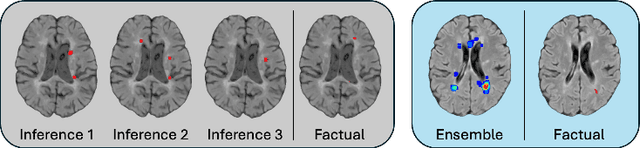

Abstract:Discriminative classifiers have become a foundational tool in deep learning for medical imaging, excelling at learning separable features of complex data distributions. However, these models often need careful design, augmentation, and training techniques to ensure safe and reliable deployment. Recently, diffusion models have become synonymous with generative modeling in 2D. These models showcase robustness across a range of tasks including natural image classification, where classification is performed by comparing reconstruction errors across images generated for each possible conditioning input. This work presents the first exploration of the potential of class conditional diffusion models for 2D medical image classification. First, we develop a novel majority voting scheme shown to improve the performance of medical diffusion classifiers. Next, extensive experiments on the CheXpert and ISIC Melanoma skin cancer datasets demonstrate that foundation and trained-from-scratch diffusion models achieve competitive performance against SOTA discriminative classifiers without the need for explicit supervision. In addition, we show that diffusion classifiers are intrinsically explainable, and can be used to quantify the uncertainty of their predictions, increasing their trustworthiness and reliability in safety-critical, clinical contexts. Further information is available on our project page: https://faverogian.github.io/med-diffusion-classifier.github.io/